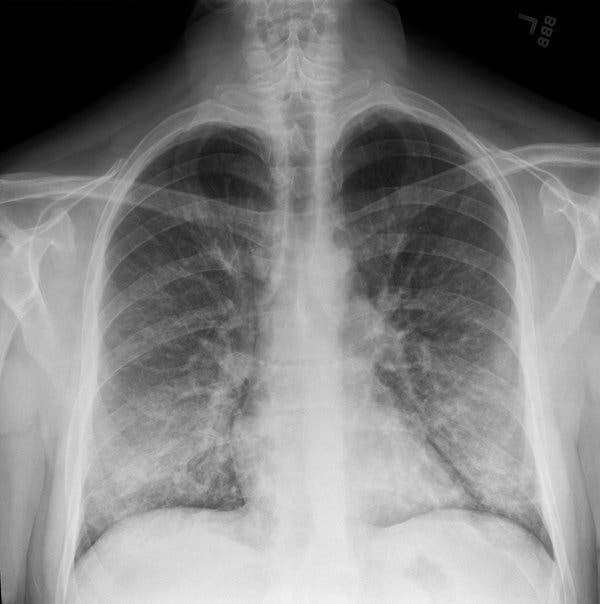

According to the Centers for Disease Control and Prevention, around 450 people across 33 states in the United States have severe respiratory illness after using e-cigarettes.

A large percentage of the patients used cannabis-derived vaping products with THC while others said they had only smoked nicotine.

No infectious causes have been identified but according to CDC, the mysterious lung illnesses ‘are likely associated with a chemical exposure.’